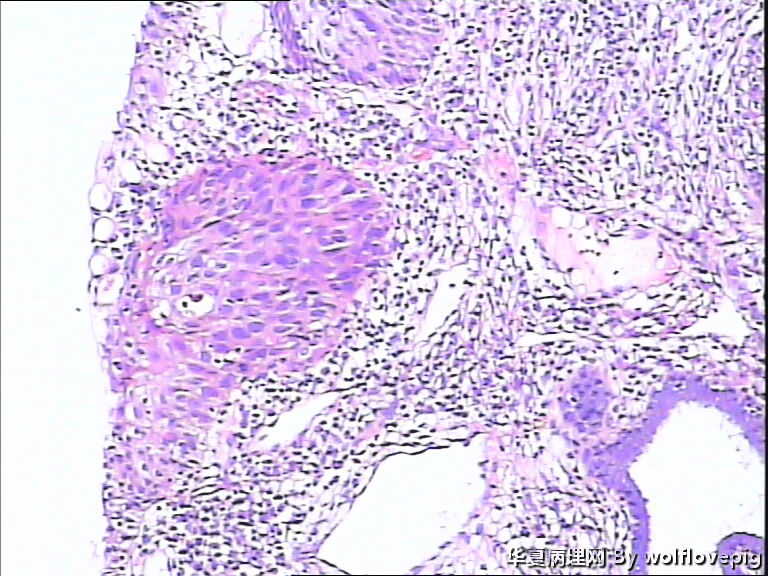

求助,宫颈!

37y

CIN3累腺

CINIII累及腺体

CIN-II 累及腺体。我看不够原位癌。学习了!

CIN2-3,累腺